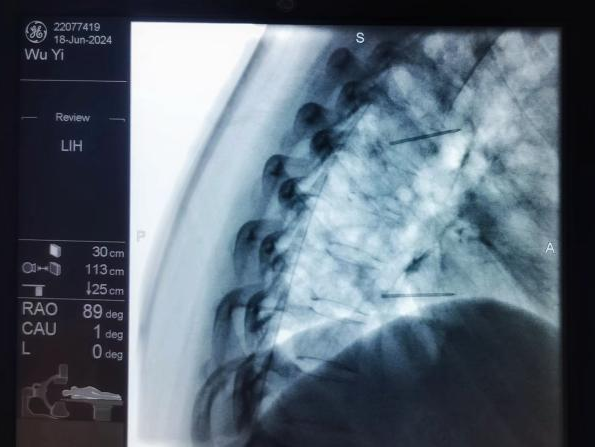

脊髓电刺激植入术:将电极植入脊柱附近硬膜外腔,通过电流刺激脊髓,阻断疼痛信号传至大脑,有效治疗慢性顽固性神经痛。

脊髓电刺激植入术